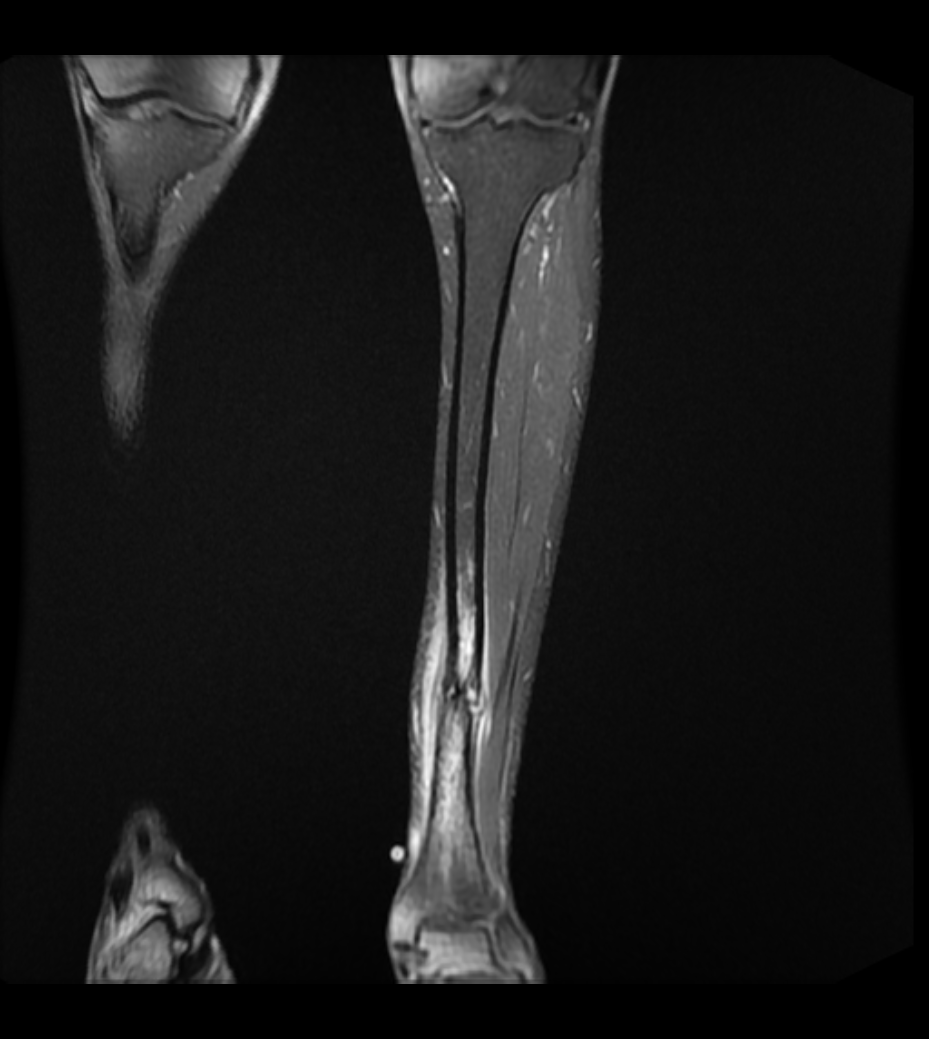

Tibial Stress Fractures

- tension side of bone / lateral side

- progression to complete fracture has been well documented in athletes